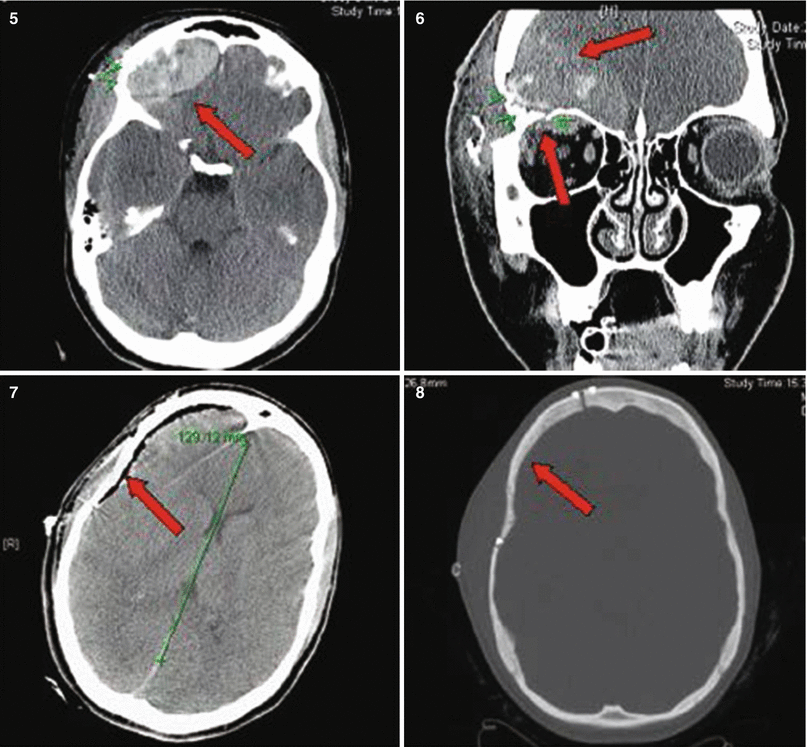

Fig. 27.1

Patient No. 1: a 22-year-old female crime victim, who sustained multiple GSW with a single non-penetrating GSW to the head. Entry wound at R cheek, exit wound on R supraorbital forefront. Plates 1 and 2: scout images A/P and lateral without evidence of bullet. Plates 3 and 4: preoperative images (bone windows) demonstrating R frontal skull fracture with pneumocephalus and orbital roof fracture. Plates 5 and 6: axial and coronal views of large R epidural hematoma and infraorbital hematoma. Plates 7 and 8: axial views of postoperative results status post evacuation of hematoma and autologous cranioplasty. Plates 9 and 10: reconstructed orbital roof status post transfrontal evacuation of retro-orbital hematoma